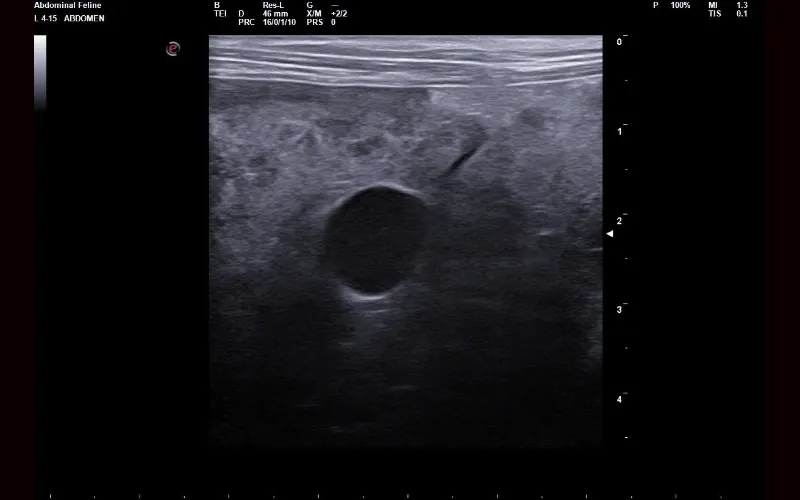

Different diseases and conditions create distinct patterns that become recognisable on ultrasound, even when physical examination or lab work has been inconclusive. Some findings are diagnostic in themselves, while others provide a strong indication of what is developing and the urgency with which it needs to be addressed.

Ultrasound allows us to examine internal organs without surgery. It helps identify changes in tissue structure and assess how organs interact with each other.

Ultrasound can evaluate abdominal organs, soft tissues and other internal structures. This imaging technique helps us look for abnormalities that may affect a cat’s health.

Ultrasound findings can clarify whether disease is localised or affecting multiple organs. This information helps us determine the most appropriate next steps for diagnosis or treatment.